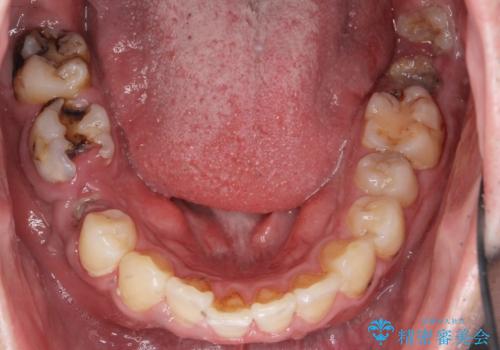

全部治療して見た目を良くしたい。

- 口の中をマスク生活の間に全て治したい、見た目を良くしたいとの事で来院。

まず徹底的に虫歯を取り除き、保存が出来ない部位は抜歯(親知らずを含む)を行い、根管治療が必要な部位は精密根管治療を行いました。